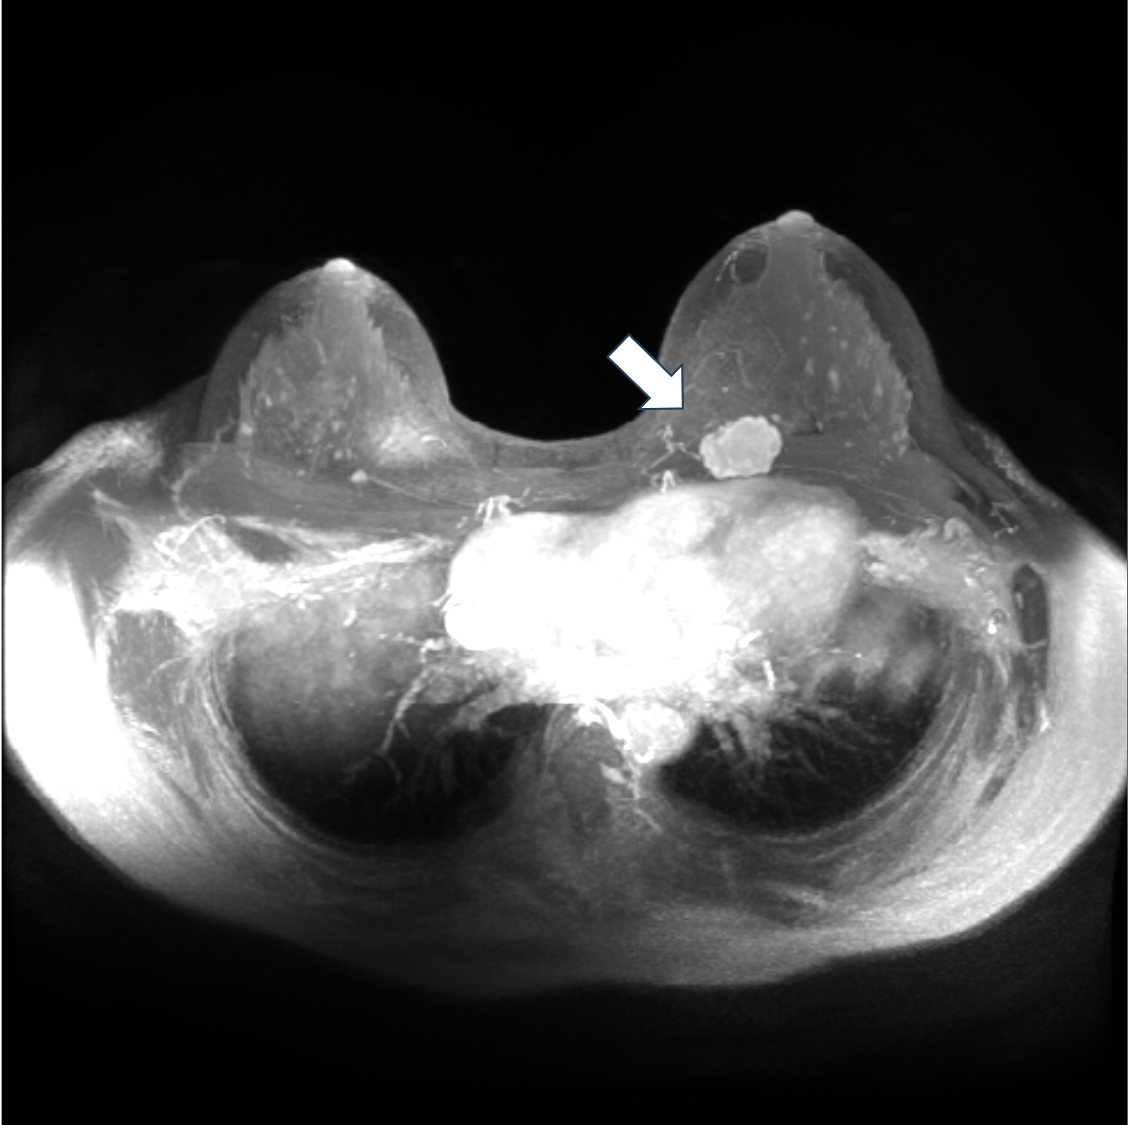

6. ダイナミックMRI 早期相 MIP像

左乳房に不整形腫瘤を認める。MIP像は一目で病変全体を把握することができる。